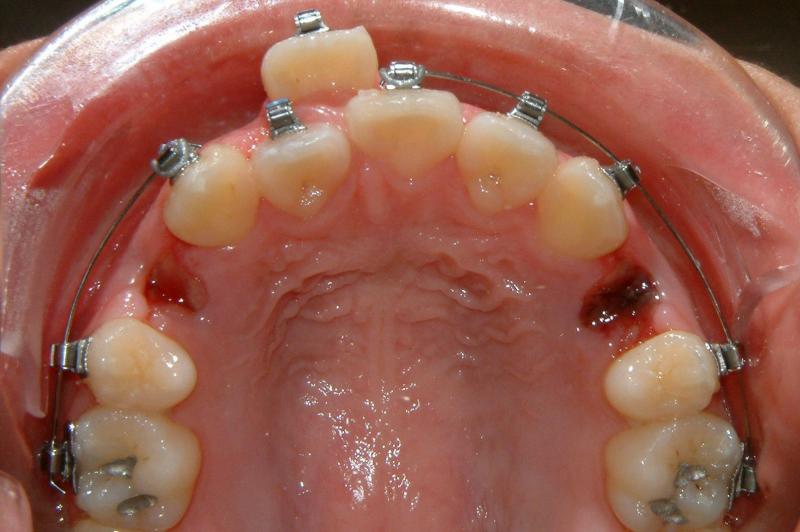

The upper right central incisor and lateral incisor form 2 rows. It would be a fatal mistake to extract either one of these two. It might be the case if the patient has no access to the correct orthodontic treatment. In this case, the 1st premolars are removed. Initial and some progress data are presented in Figs. 1-5.

Fig. 4 Problem resolved after 20 months (progress) -- front view

Fig. 5 Problem resolved after 20 months (progress) -- occlusal view